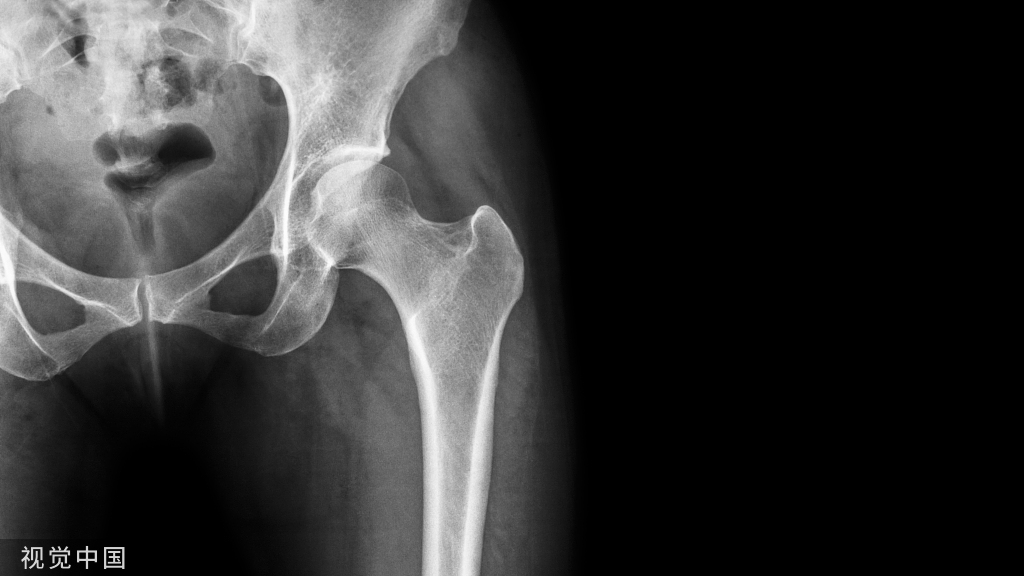

对于A1.3型骨折,单纯牵引很难复位通常需要借助骨钩来复位,主要是由于小粗隆完整受到肌肉的牵拉而移位

可以在偏前方植入一枚克氏针临时固定来进行复位辅助